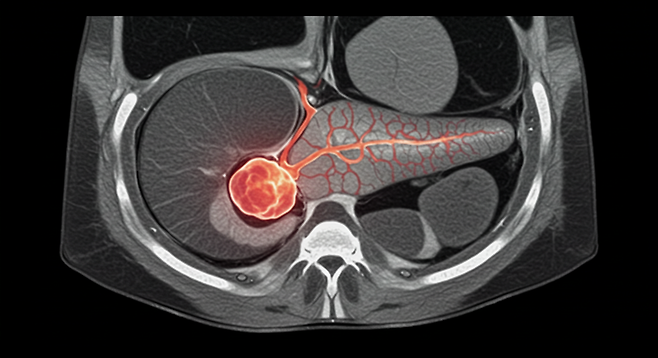

췌장은 우리 몸에서 소화 효소와 호르몬(인슐린)을 생산하는 중요한 장기입니다. 췌장염은 이러한 췌장에 염증이 생기는 질환으로, 초기에는 증상이 미미하여 간과하기 쉽습니다. 하지만 방치하면 심각한 합병증을 초래할 수 있으므로, 초기 증상을 인지하고 적절한 대처를 하는 것이 중요합니다.

췌장염, 왜 생기는 걸까요?

- 즉시 병원 방문: 소화기내과 전문의에게 진료를 받고 정확한 진단을 받아야 합니다. 혈액 검사, 복부 CT, MRI 등의 검사를 통해 췌장염 여부와 원인을 확인할 수 있습니다.